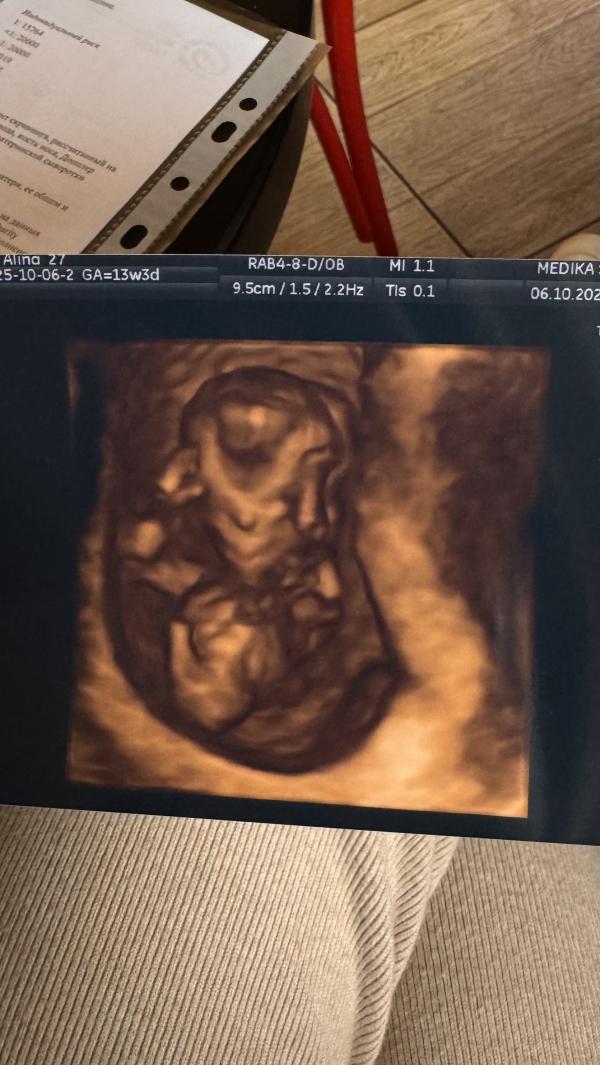

Прошла первый скрининг! 🥳

И в итоге ВСЁ ХОРОШО! 🎉🥹❤️

Малыш растёт, все сформировалось для данного этапа верно, можно сделать огромное и громкое ФУХ 😌 Никаких противопоказаний для занятий в зале тоже нет, поэтому угощаю себя пироженкой и отмечать на силовую тренировку💪🏽

P.s. после потери прошлой беременности в 1 триместре, в этот раз как на иголках.